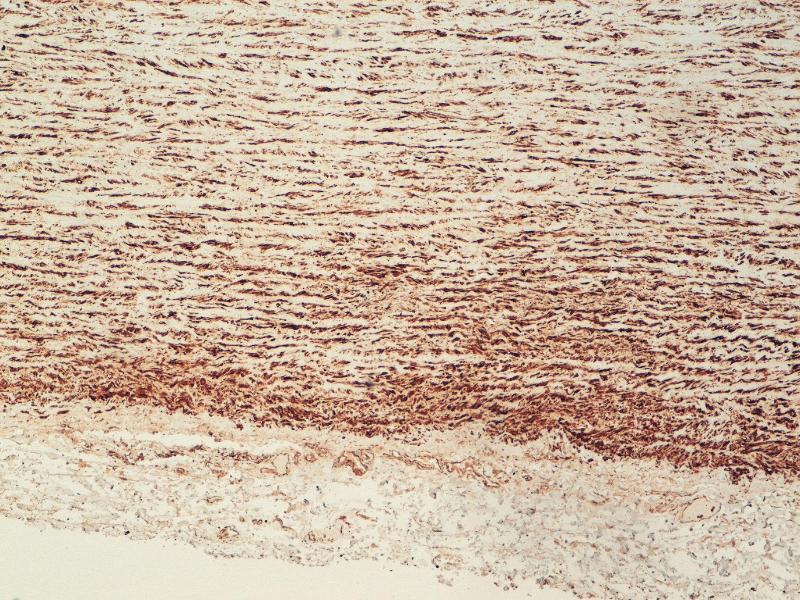

alpha Actinin 抗体

This 小鼠 单克隆 antibody specifically detects alpha Actinin in WB 和 IHC. It exhibits reactivity toward 人.

Western Blotting (WB), Immunohistochemistry (IHC)

CB11